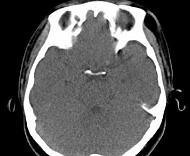

问题 女,31岁,在左眶外上缘发现一包块,质软,余所见无明显异常.如图所示病灶应诊断为()

选项 A.畸胎瘤 B.错构瘤 C.脂肪瘤 D.表皮样囊肿 E.淋巴管瘤

答案 C